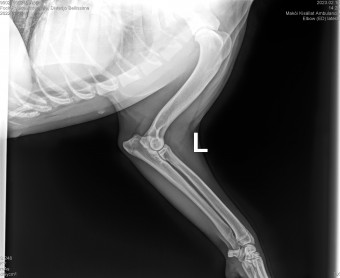

DIVLADJO BELLISSIMA

( BELLISSIMA )

Data nasterii:

07.02.2022